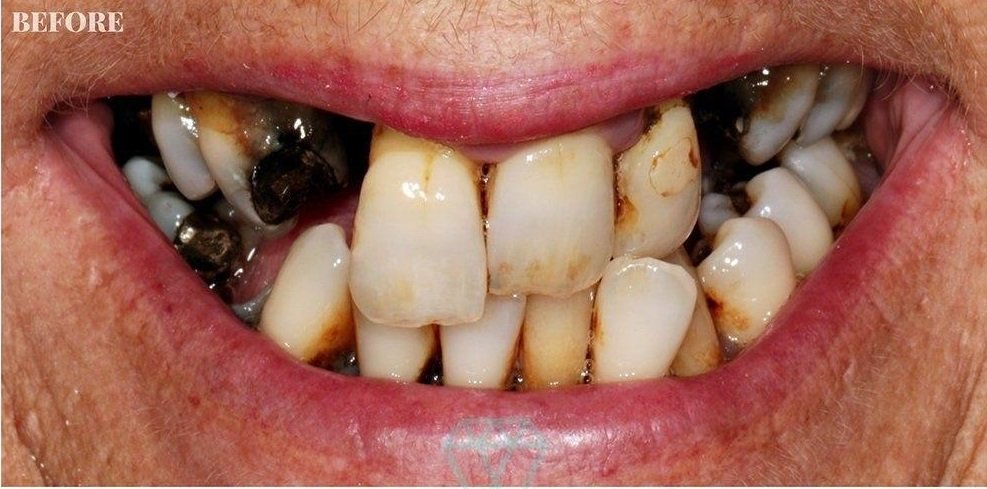

Rudra Dental Clinic, located in Hadapsar, Pune, is a trusted destination for comprehensive and advanced dental care. Led by Dr Disha K. Prajapati, who brings over 19 years of clinical experience, the clinic is committed to delivering high-quality treatments with a patient-first approach. From routine dental checkups and teeth cleaning to specialized procedures like root canal treatment, dental implants, braces, and smile designing, every service is provided with precision, care, and modern technology. The clinic focuses on maintaining hygiene, safety, and a comfortable environment for patients of all age groups.

At Rudra Dental Clinic, the goal is not just to treat dental problems but to create healthy, confident smiles. Dr Disha K. Prajapati and her team take time to understand each patient’s needs and offer personalized treatment plans that ensure long-term oral health. Known for painless procedures and transparent consultation, the clinic has built strong trust among patients in Hadapsar and nearby areas. Whether it’s preventive care or cosmetic dentistry, Rudra Dental Clinic stands as a reliable choice for complete dental solutions..

clinic offers a wide range of services including root canal treatment, dental implants, braces, teeth cleaning, smile designing, tooth extraction, and preventive dental care.